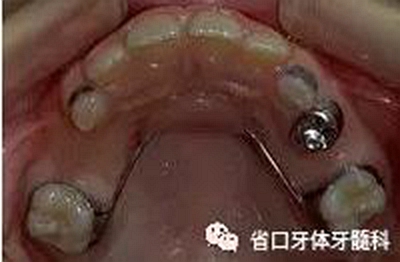

丝圈式保持器适用于以下三种情况:单侧第一乳磨牙早失;第一恒磨牙萌出后,第二乳磨牙单侧早失;双侧乳磨牙早失,用其他间隙保持器困难者。

间隙保持器由不锈钢和(或)塑料制成。分为活动式和固定式(粘在儿童口内)间隙保持器。乳磨牙早失者,可根据情况选择丝圈式保持器、舌弓保持器、Nance 弓保持器或者可摘义齿保持器等。